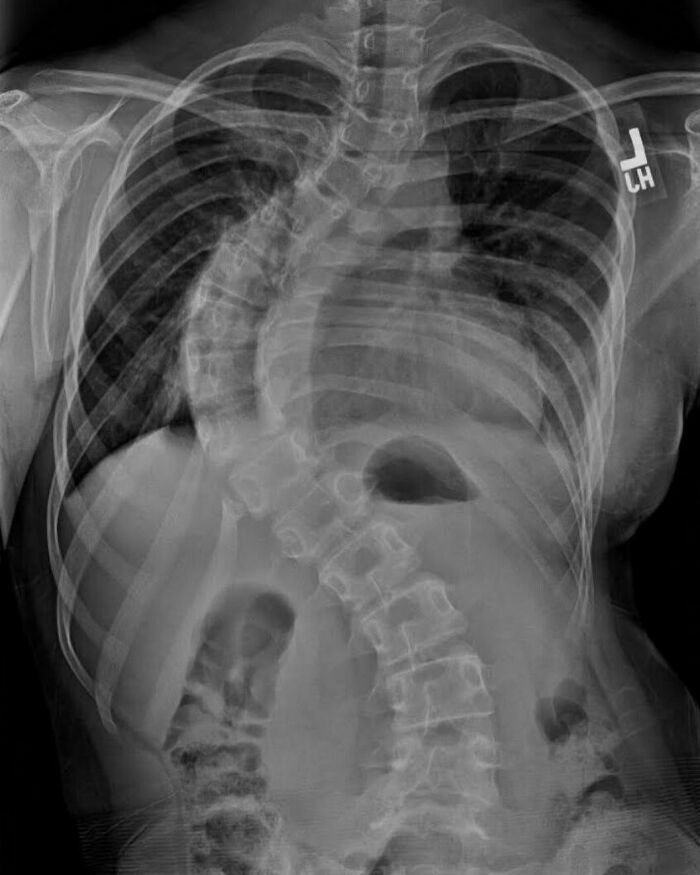

Cuerpo plagado de parásitos como resultado de comer carne de cerdo cruda durante 10 años. La triquinelosis, más comúnmente conocida como triquinosis, es una enfermedad parasitaria transmitida por los alimentos que se produce por comer carnes crudas o poco cocidas, en particular productos de cerdo infestados con larvas de un tipo de gusano redondo llamado Trichinella. Cuando un humano o un animal come carne que contiene larvas infecciosas de Trichinella, el ácido del estómago disuelve la cubierta dura del quiste alrededor de las larvas y libera los gusanos. Los gusanos pasan al intestino delgado y, en 1 o 2 días, maduran. Después del apareamiento, las hembras adultas ponen huevos. Los huevos se desarrollan en gusanos inmaduros, viajan a través de las arterias y son transportados a los músculos. Dentro de los músculos, los gusanos se enrollan en una bola y se enquistan (quedan encerrados en una cápsula). El ciclo de vida se repite cuando la carne que contiene estos gusanos enquistados es consumida por otro humano o animal.